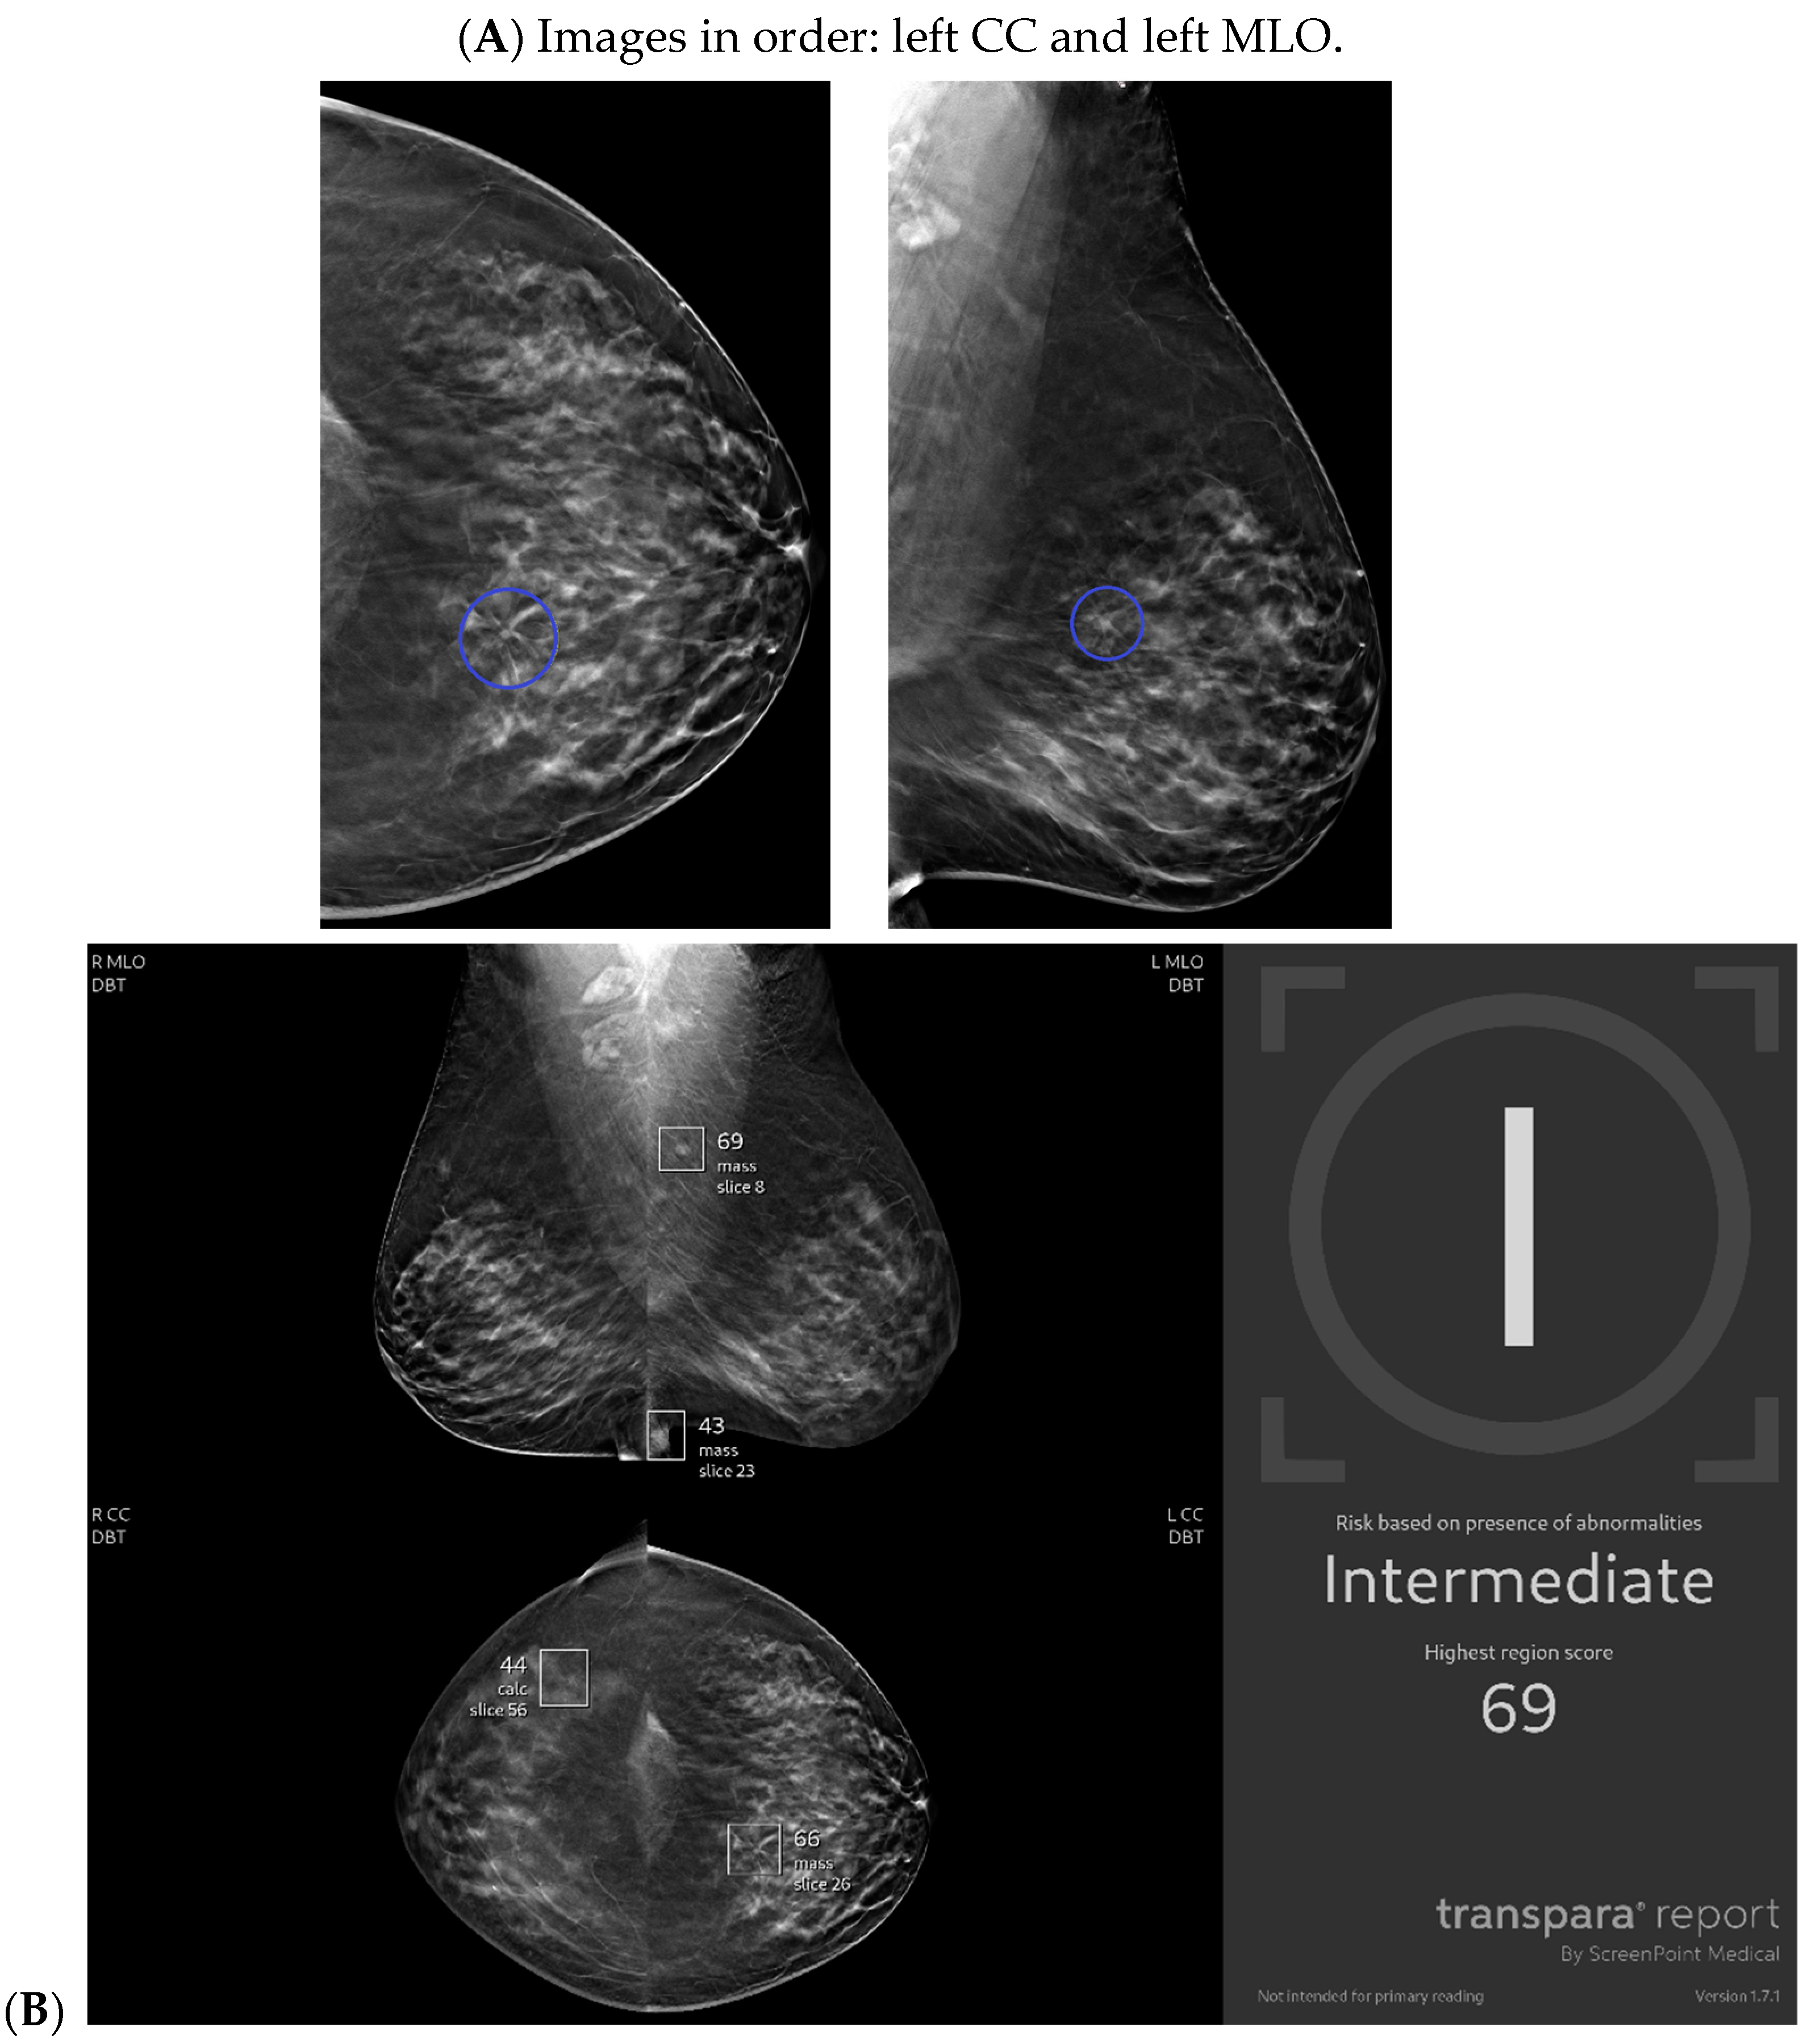

Figure 2.

New architectural distortion detected by artificial intelligence (AI): A patient in her 50s’ screening mammogram revealed a new area of architectural distortion (circle) in the inner central region of the left breast (A). The AI program Transpara highlighted potential regions of interest, including this suspicious area of architectural distortion on the left breast on the corresponding left CC view; however, AI also highlighted benign areas that were arbitrated out by the radiologist (B). There was no sonographic correlate, so a stereotactic biopsy of this area of architectural distortion was then biopsied under guidance. Pathology yielded invasive lobular carcinoma. Images obtained from the Icahn School of Medicine at Mount Sinai.